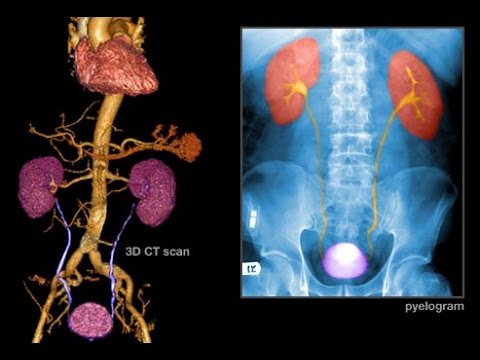

Exactly what is Bladder Cancer?Cancer is The expansion of

irregular cells in your body. Bladder cancer typically commences

while in the internal lining from the bladder, the organ that stores urine just after it passes with the kidneys. Most bladder cancers are caught early, when therapies are extremely successful and the disorder hasn’t spread further than the bladder. But bladder most cancers tends to come back, so common Check out-ups are essential.